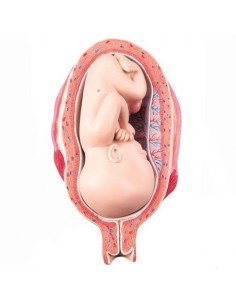

3B Modèle anatomique scientifique du bassin gravide, décomposable en 3 parties L20

3B Bassin scientifique, anatomique Modèle pour illustrer l'accouchement L30